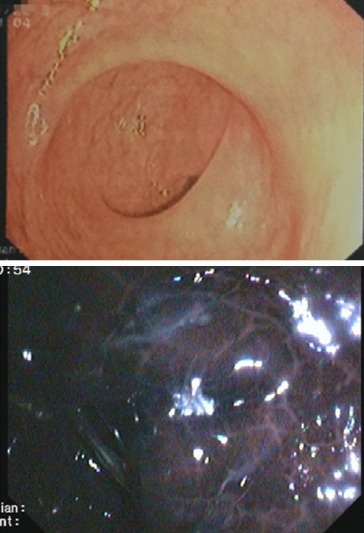

结肠镜检查

40岁做首次肠镜检查+结肠镜是一根软管

做肠镜切除手术 后照肠镜顺便割了几个息肉_健

症性疾病如溃疡性结肠炎

【肠镜检查痛苦吗】肠镜检查痛吗_做电子肠镜

照肠镜的时候我看到大肠里面很干净,为什么还

799人照肠镜就有51个患癌!预防大肠癌看这里

23岁女子肠镜照出黑蛇皮状

我想问。照肠镜照胃镜是什么感觉